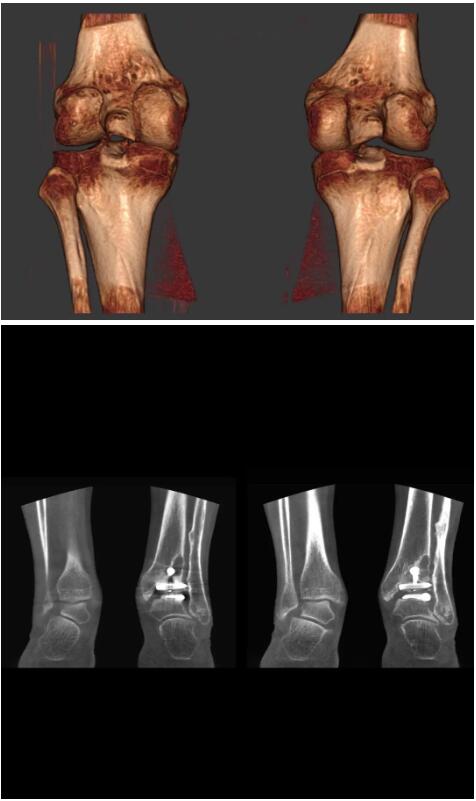

比如上面這款專用于足部和踝部掃查的CT成像系統(tǒng),患者在進行CT掃查時只需要站在上面即可,雙腳站或者單腳站都可以,當然,如果患者不是那么方便站著做完CT掃查,也可坐在上面。

這款CT掃查系統(tǒng)自帶屏蔽裝置,它的體積非常小,僅需要極小的空間即可,并不像常規(guī)CT那樣需要一間單獨的檢查室。此外,這種CT掃查的速度非??欤瑑H需30秒左右可以完成檢查,輻射劑量相對常規(guī)的CT要少許多,尤其適合醫(yī)院的骨科使用。

而患者站著做足部或者踝部做CT檢查還有個好處是,可以檢查患者在負重的情況下,骨關節(jié)的真實情況,而躺著做CT掃查時未必能看出來。負重CT掃查特別是對于受傷的運動員或者舞蹈員來說意義更大,能夠更準確地評估傷情,幫助他們盡早復原。

以下是這些“特立獨行”的CT所拍出來的圖像: